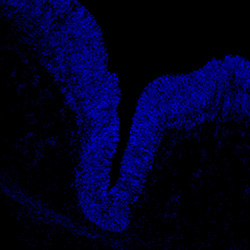

DAPI

7PCW human midbrain